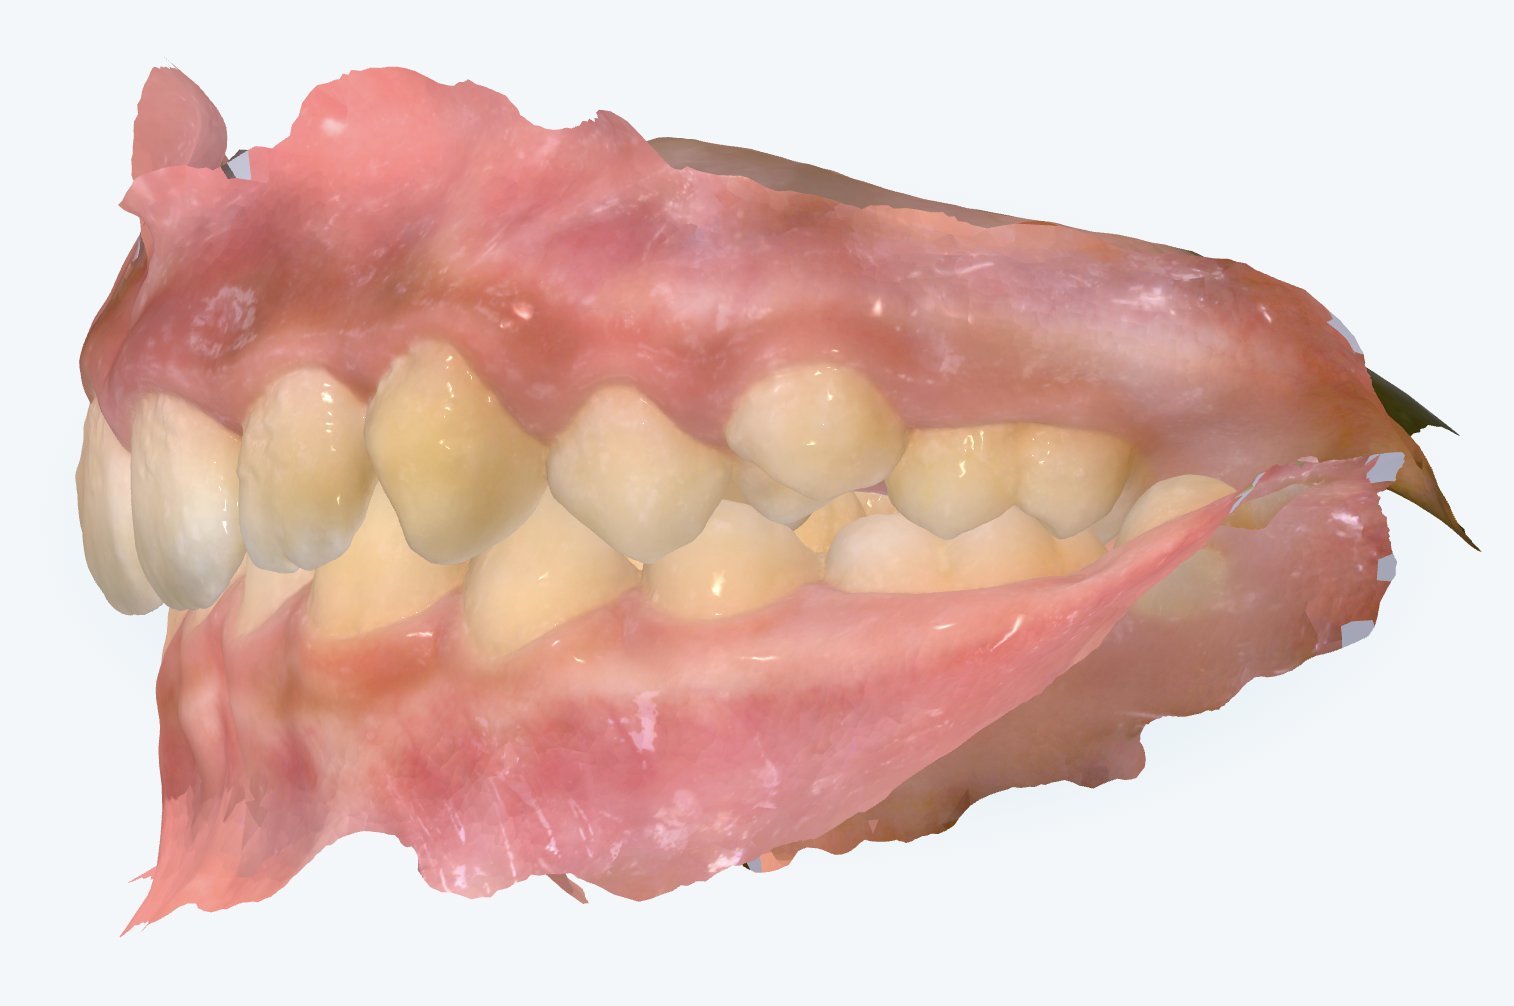

初診時の画像診断

上の前歯が後方に傾くことで前歯が噛んでいます。前歯が後方に傾くことで噛み合わせが深くなっています。

特に上の前歯は、噛み合わせを保とうとして内側に傾いており、その結果、歯茎が見えやすくなったり、前歯が長く伸びたように見えたりしています。

下の歯が足りないため、上の前歯がなんとか噛もうと手前に大きく傾いています。そのため噛み合わせが深くなったり、前歯の出っ歯感が強調されています。奥歯のかみ合わせ自体はとても良好なので、前歯の本数を上下で合わせるために、上の歯(小臼歯)を1本抜いて本数をそろえるというのが治療方針の選択肢になります。そうすることで、上の前歯の傾きを正しい位置に整えながら、上下で自然に噛み合うようにしていくことが重要になります。